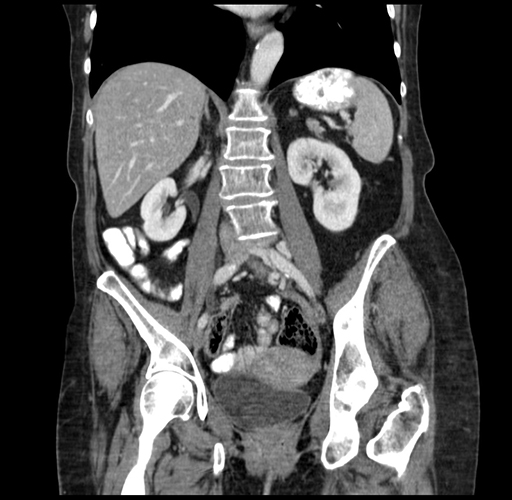

Axial Venous

Coronal Venous